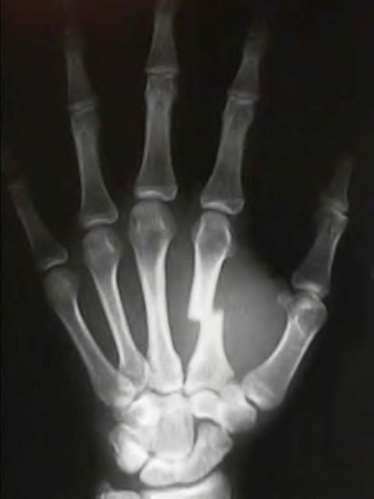

A 20-year-old park ranger trips and falls onto his right wrist with the wrist in extension and pronation. The local urgent care orders both radiographs and a CT, which you review and determine to be normal. The patient complains of ulnar-sided wrist pain. On exam, his tenderness is localized to the fovea. Ulnar deviation also causes him pain. There is no snapping sensation with wrist supination, flexion, and ulnar deviation. He otherwise has 5/5 strength to his first dorsal interosseous muscle with 4mm static two-point discrimination on the ulnar side of the 4th digit. Which of the following injuries is most likely responsible for his symptoms and exam?